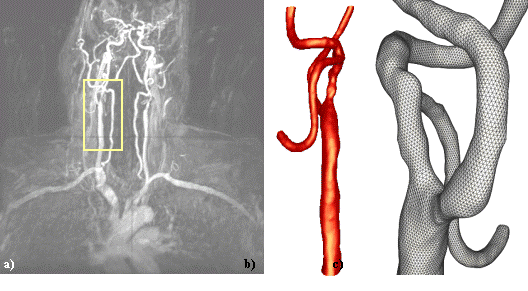

A second case illustrates the use of adaptive background

grids to specify an element size distribution that depends

on the local surface curvature. Fig. 7a and 7b show the

MIP of the MRA images from two different viewpoints. The

reconstructed model is shown from similar viewpoints in

Fig. 7c and 7d.

a) b)

c) d)

Figure 7. Circle of

Willis model reconstructed from MRA images: a) and b) MIP

projections from different viewpoints; c) and d) reconstructed

model from similar viewpoints.

A close-up view of the triangulation of the final model

is shown in Fig. 8a. This triangulation was then used to

refine an adaptive background grid based on its local curvature

in order to specify an element size distribution that yields

roughly the same number of elements across any cross-section

of the model. The generated finite element grid (Fig. 8b)

contained approximately 1 million elements.

a)

b)

Figure 8. Finite element

mesh of the circle of Willis: a) surface triangulation of

the final geometrical model; b) surface of the finite element

grid generated using adaptive background grids to specify

an element size distribution that depends on the local surface

curvature.